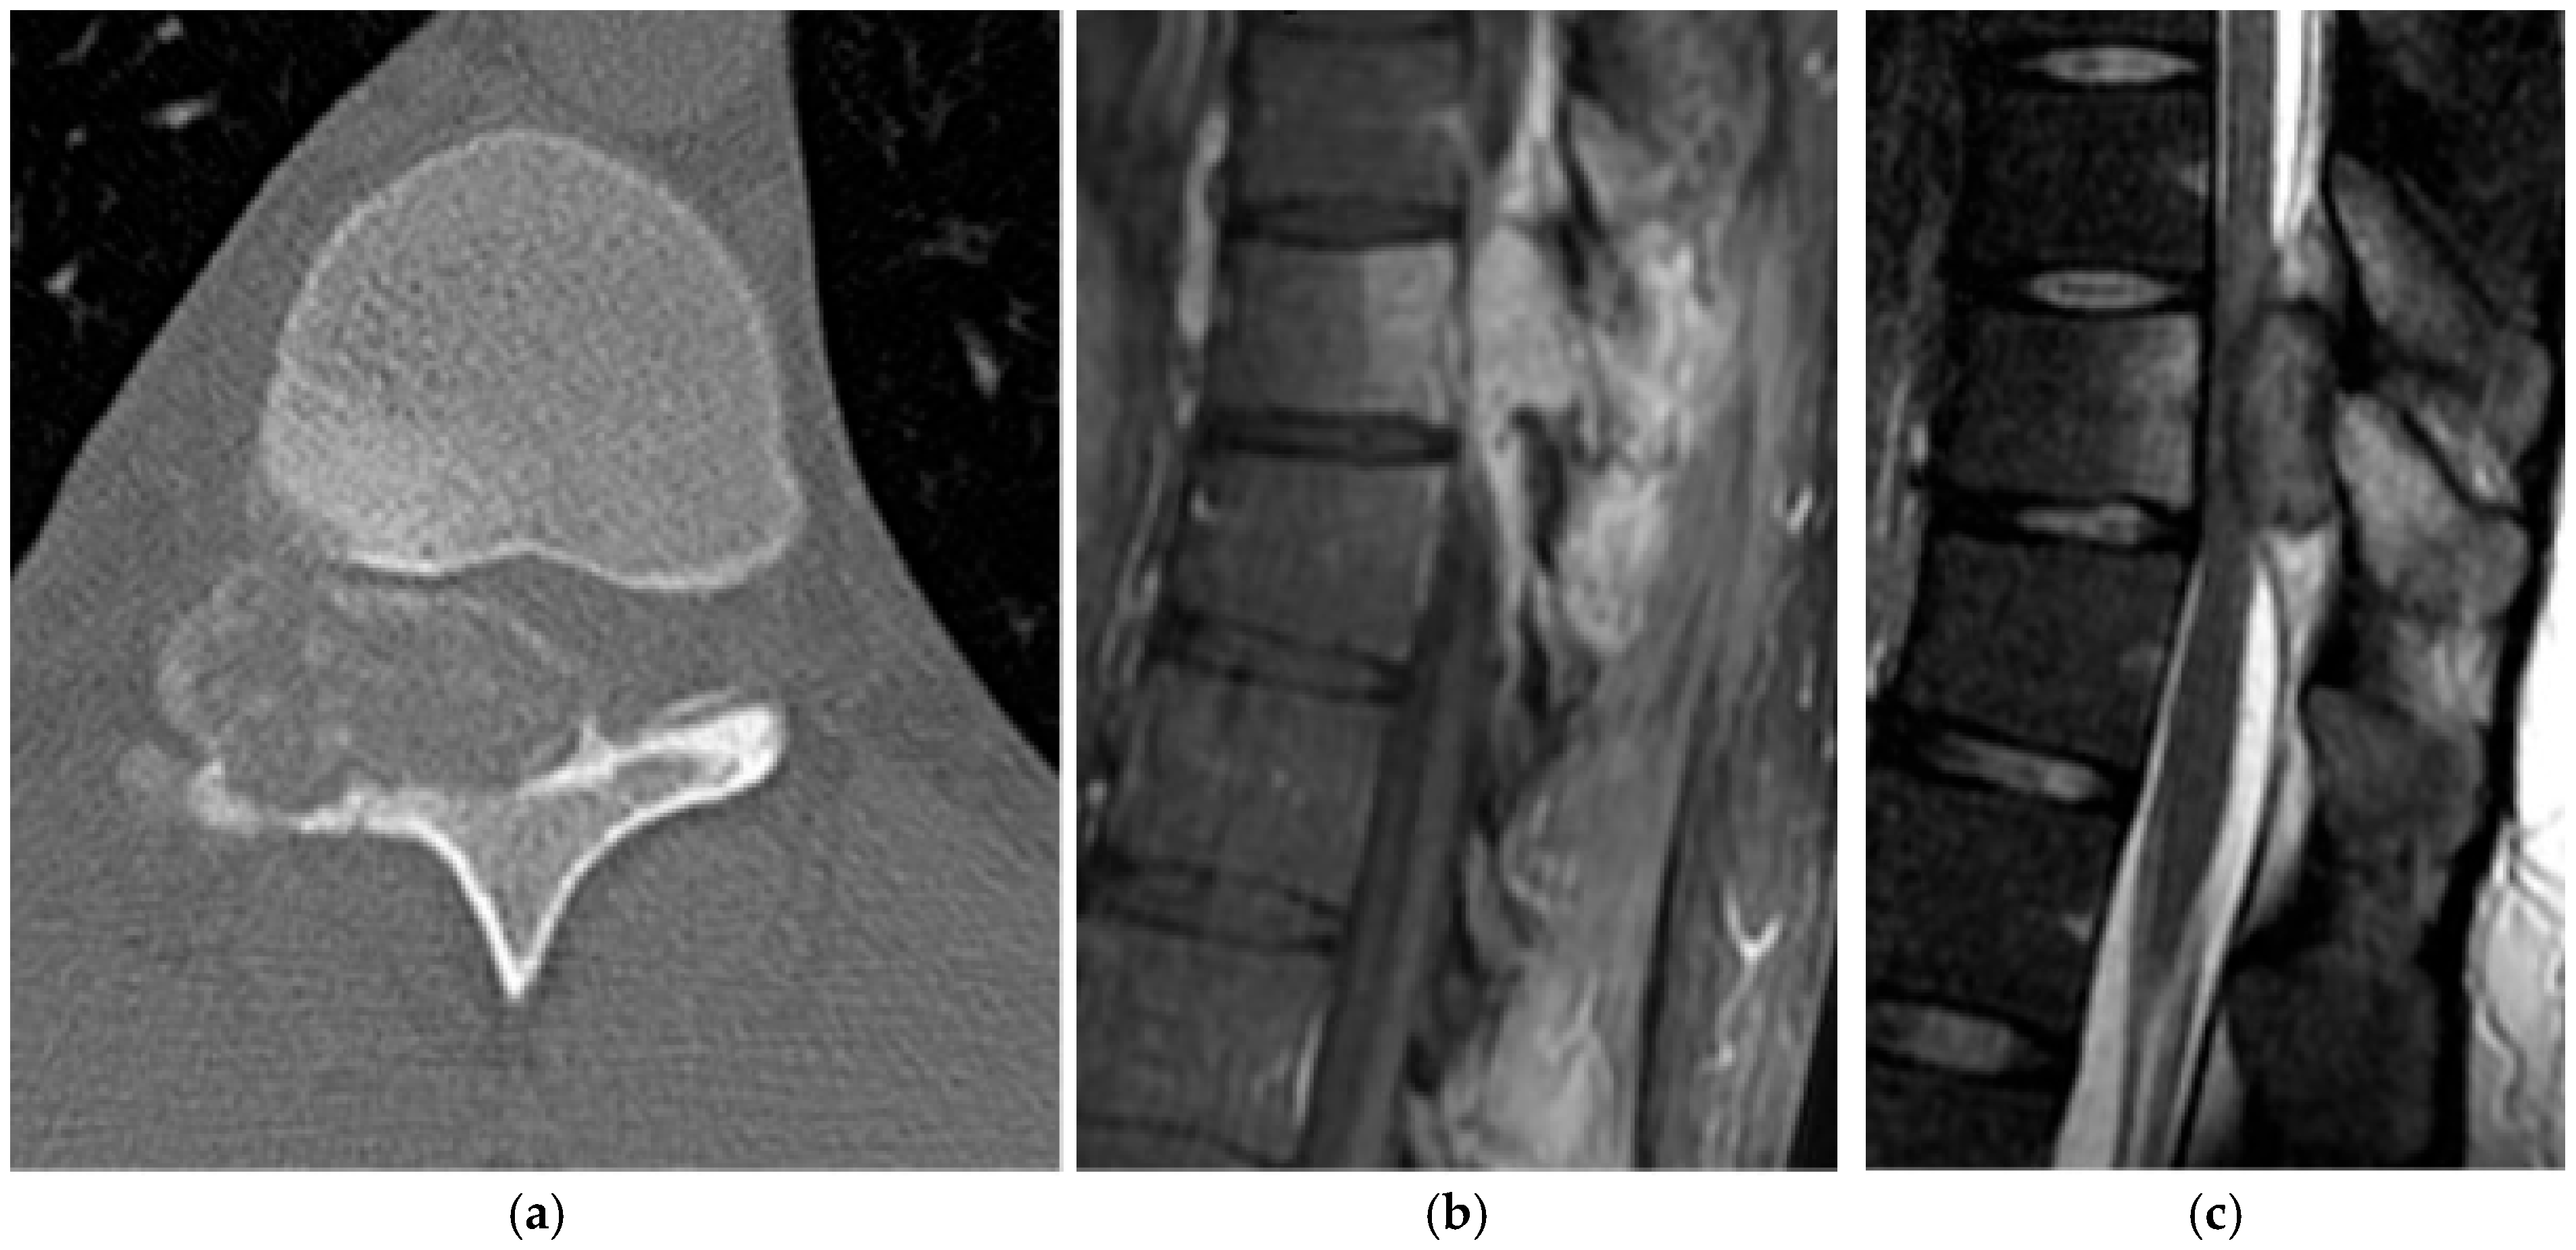

2.3.2. Chordoma